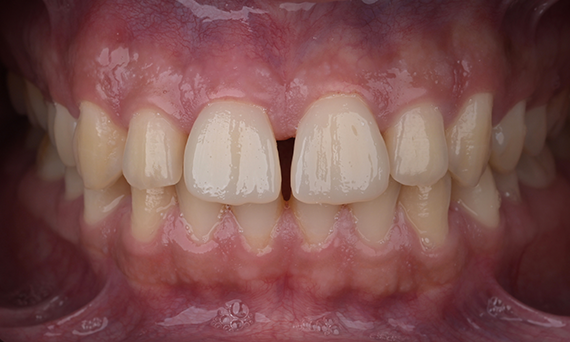

Minimal Preparation Veneers after Trauma of Upper Central Incisors

Restoration with a highly esthetic material in one day after trauma to the maxillary central incisors.

Before: Clinical Situation pre-op. Trauma of upper central incisors

After: Adhesively bonded restorations.

Dr. Mohamed Hassanien

Cairo, Egypt